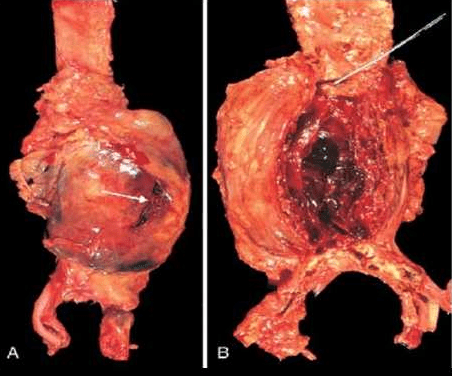

Атеросклеротичните аневризми на абдоминалната аорта могат да достигнат големи размери – до 15см в най- широката си част и до 20-25 см по дългата си ос. По интималната им повърхност се наблюдава изобилие от атеросклеротични плаки, често с насложени пристенни тромби с различна големина и давност.

Обикновено имат сферична форма и разширението на съда е само от едната страна. Типичният за третичният сифилис облитеративен ендартериит на малките съдове може да се развие навсякъде в тялото, но една от най-характерните му клинико-морфологични изяви е засягането на vasa vasorum на аортата, последвано от луетичен аортит. Деструкцията на аортната медия води до аневризмално разширение, локализирано ( за разлика от повечето атеросклеротични аневризми) във възходящата част на аортата. Аневризмата може да достигне 15-20 см в диаметър. Интималната й повърхност е с характерния за луетичен аортит изглед на “кора на дърво” или “портокалова кора”, в резултат на фиброзирането на съда вследствие възпалението на vasa vasorum.